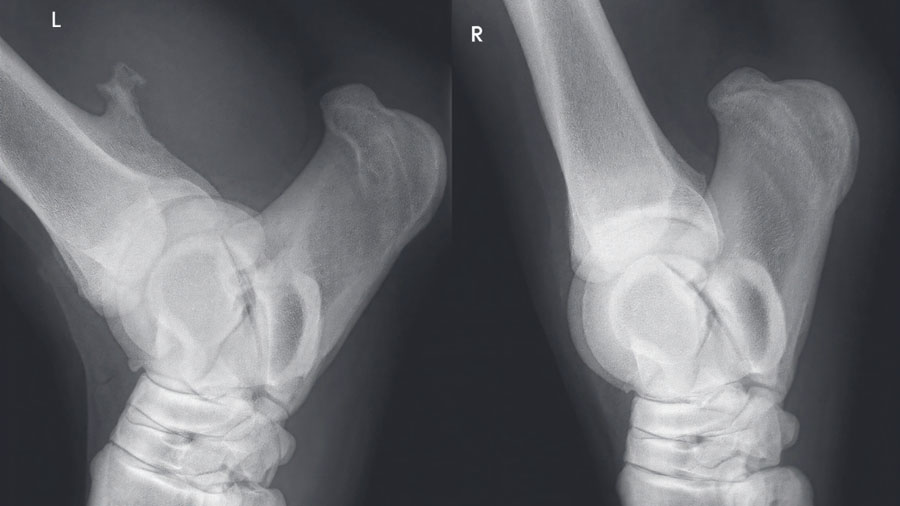

Radiography and ultrasonography are often used for primary investigation and can be easily misinterpreted.

Due to the concave aspect of the caudal radius at the level of the distal physis, axial spikes can be hidden by the more prominent medial and lateral extent of the physis, making them difficult to appreciate on standard projections. Equally, the medial and lateral physeal “scars” can be misinterpreted as spikes.

Representative clinical case

A recent case involved a 3‑year‑old Thoroughbred gelding with acute lameness and carpal sheath swelling, having successfully completed multiple races. Radiographs identified a large osteochondroma, and ultrasound confirmed marked disruption to the DDFT. Standard tenoscopic surgery was completed as above, identifying the osteochondroma extending deep into the DDFT. Removal was confirmed using radiography intra-operatively after debridement of the tendon lesion.